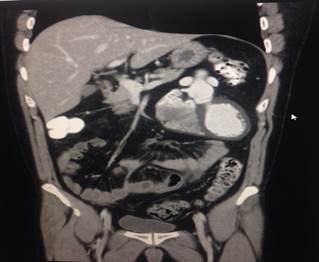

En la tomografía axial computada (TAC) y contrastada de abdomen aparecen el corazón y los grandes vasos en el abdomen superior izquierdo entre el estómago, duodeno e hígado y que fueron informadas por imagenología (Figura 3).

No contamos con la imagen de ultrasonografía (USG) abdominal donde se miraba el corazón y grandes vasos en plena actividad.